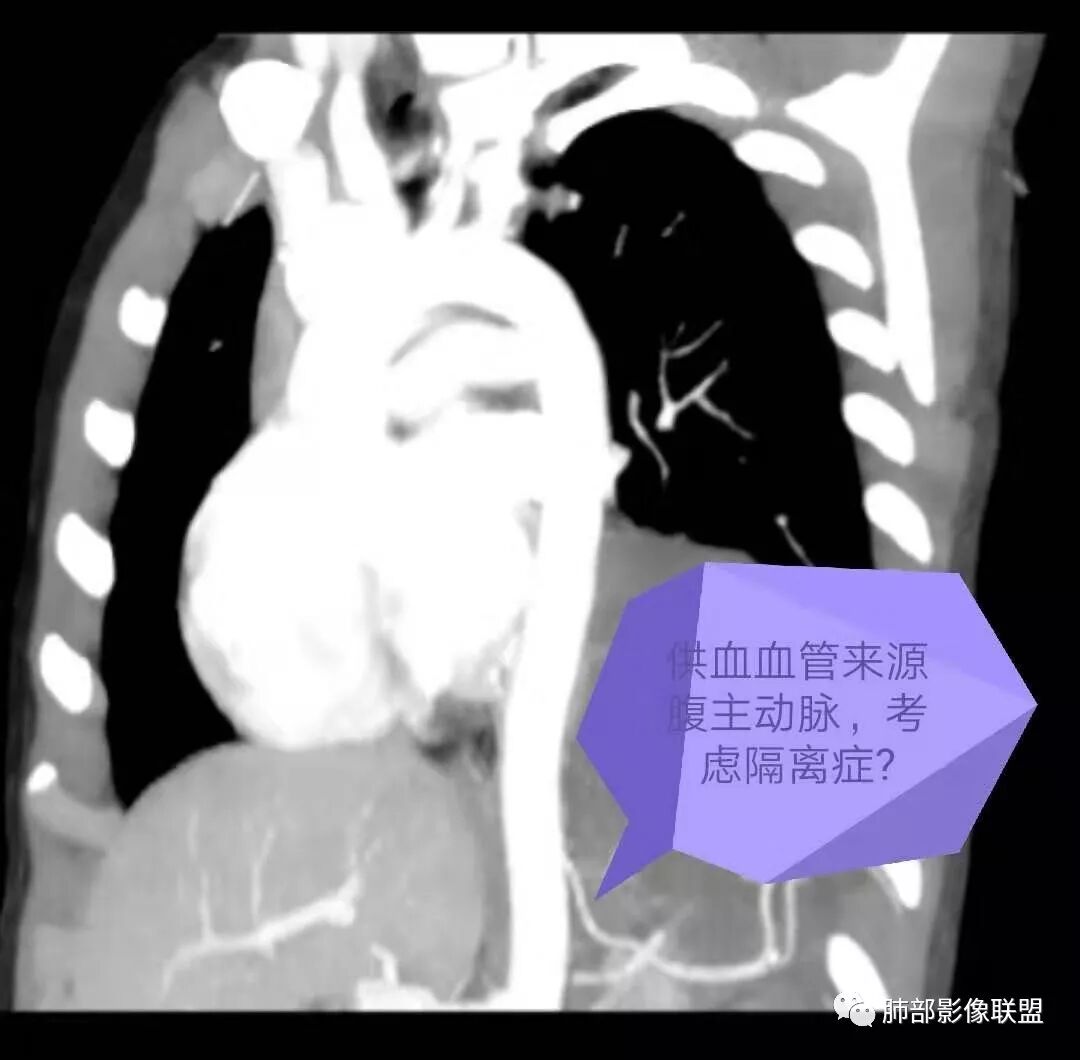

肺隔离症,供血动脉来源腹主动脉

左下肺囊性占位,多发分隔,增强分隔及边缘强化,腹主动脉供血,考虑肺隔离征。

左肺下叶占位,内部多发分割,内部可见供血血管(似来自腹主动脉分支),考虑:隔离症可能

左肺下叶囊性变,可见多发分隔,增强后分隔及边缘可见强化,并可见降主动脉分支进入,考虑叶外型肺隔离症

电话随访,患者在西安某医院手术,为肺隔离症,供血两支动脉,均来自腹主动脉,引流入肺静脉。